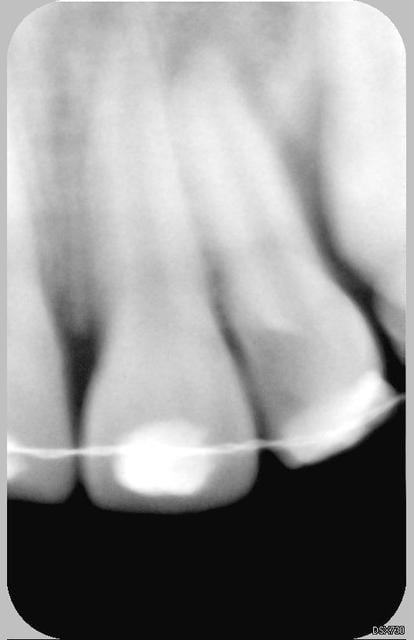

Patiente de 11 ans ayant la 21 expulsée début avril 2006. La dent a été repositionnée en centre de soins. Dans un premier temps, pas de perte de sensibilité. Puis dans un deuxième temps, comme un goût de ça tourne mal avec certainement rhyzalyse interne de la 22 (traitement thermafil pas d'école).

Ci joint la première radio de ces dents avec attelles centre de soins universitaire